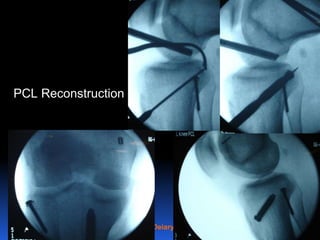

21

PCL Reconstruction

Surgical reconstruction

Indications

 Acute combined injuries

 Acute bony avulsion

 Symptomatic chronic PCL injuries that failed rehabilitation.

 There is no difference in clinical outcome between single and

double bundle PCL reconstruction.